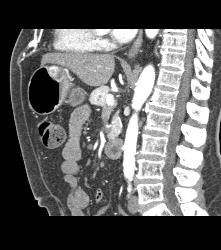

Glomus Tumor